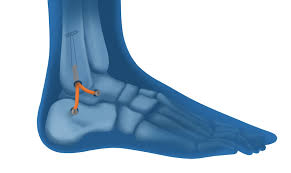

Instabilite De Cheville Dr Julien Batard

visitez l'article complet ici : https://www.orthopedie-montpellier.fr/instabilite-de-cheville/

La cheville est stabilisée par un ligament externe constitué de 3 faisceaux, et du ligament interne. Chaque ligament a des millions de terminaisons nerveuses traversant les fibres de collagène. Il existe deux ligaments principaux au niveau de la cheville, un ligament latéral externe (lle) et un ligament latéral interne (lli) situés de chaque côté de la cheville, ils sont tendus entre le tibia/péroné en haut et l'astragale/calcanéum en bas.